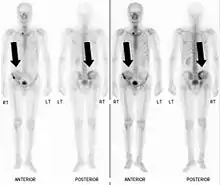

Bone scintigraphy

Also known as a bone scan, bone scintigraphy involves the injection of a small amount of radioactive tracer into the bloodstream. This tracer decays and emits radioactive energy which can be detected by a special camera. The camera produces a black and white image where areas shown as dark black indicate bone damage of some kind. If there is a black spot in the lumbar vertebrae (e.g. L5) this indicates damage and potentially spondylolysis. If this test is positive, a CT scan is usually ordered to confirm spondylolysis.[13]

Computed tomography

Commonly known as a CT Scan or CAT scan, this form of imaging is very similar to x-ray technology but produces many more images than an x-ray does. The multiple images produce cross-sectional views not possible with an x-ray. This allows a physician or radiologist to examine the images from many more angles than an x-ray allows. For this reason the CT scan is much more accurate in detecting spondylolysis than an x-ray. Bone scintigraphy combined with CT scan is considered the gold standard which means that it is best at detecting spondylolysis.[13][15]